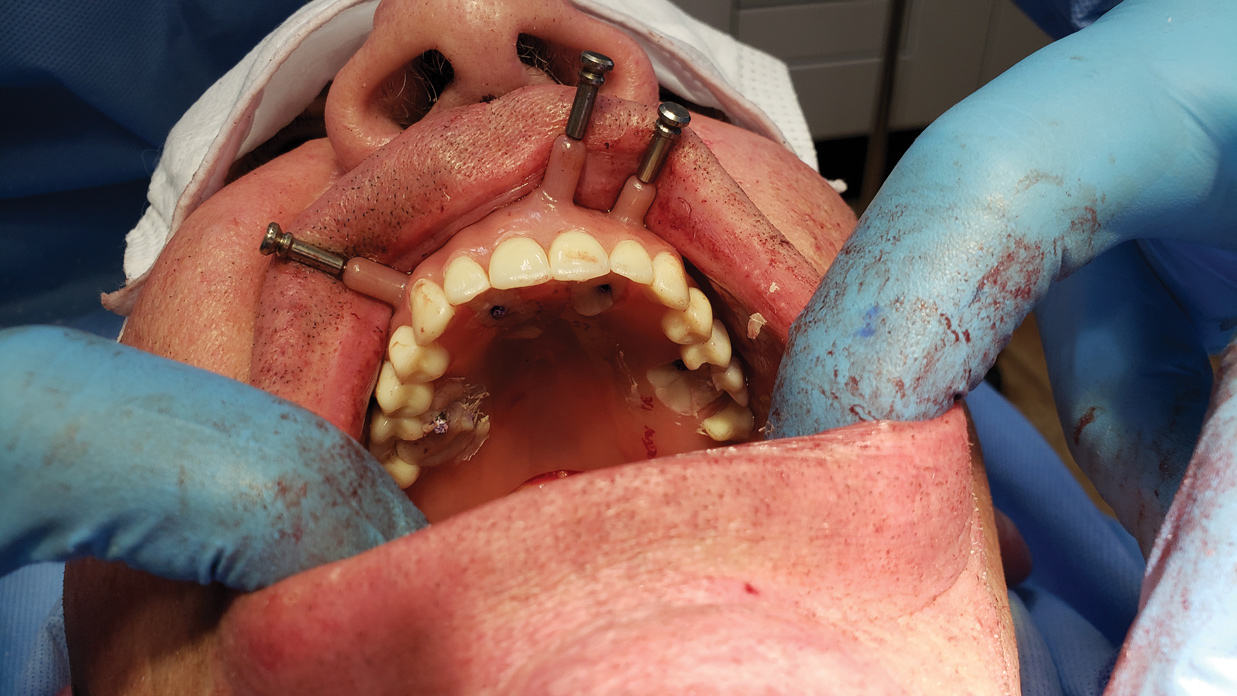

The second patient appointment includes any planned extractions and the surgical placement of implants using dynamic navigation that follows the virtual implant plan (Figure 8). After the implants are placed, any planned alveoloplasty is made using the implant shoulders as the guide for the reduction. Bone mill guides can be installed to protect the implant connection during the reduction. Any planned transmucosal abutments are connected. Temporary copings are also connected (Figure 9). The conversion denture is tried in to confirm that copings are positioned in the premilled openings in the conversion denture (Figure 10 and Figure 11). Using the occlusal locks and positioning handle, the temporary copings are picked up while the patient is set into static occlusion using autopolymerizing resin. After the resin is cured, the conversion denture is unscrewed from the patient and refined chairside. The soft tissue flaps are sutured, and the finished, polished conversion prosthesis is delivered (Figure 12 and Figure 13).

Figure 10: The conversion denture is tried in over the titanium temporary cylinders to ensure it can be properly seated in the patient’s mouth.

Figure 10

Figure 11: It is important to ensure the conversion denture can align with the opposing dentition using the occlusal locks prior to pick-up.

Figure 11